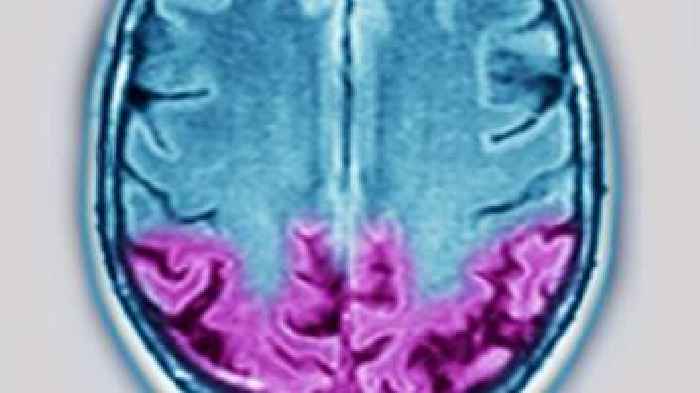

Ataxie: Symptome, Ursachen, Folgen und wann Sie zum Arzt müssenAtaxie ist eine neurologische Störung, bei der Bewegungen und Gleichgewicht unkoordiniert wirken, Betroffene gehen oft unsicher, schwanken stark und haben ein erhöhtes Sturzrisiko.